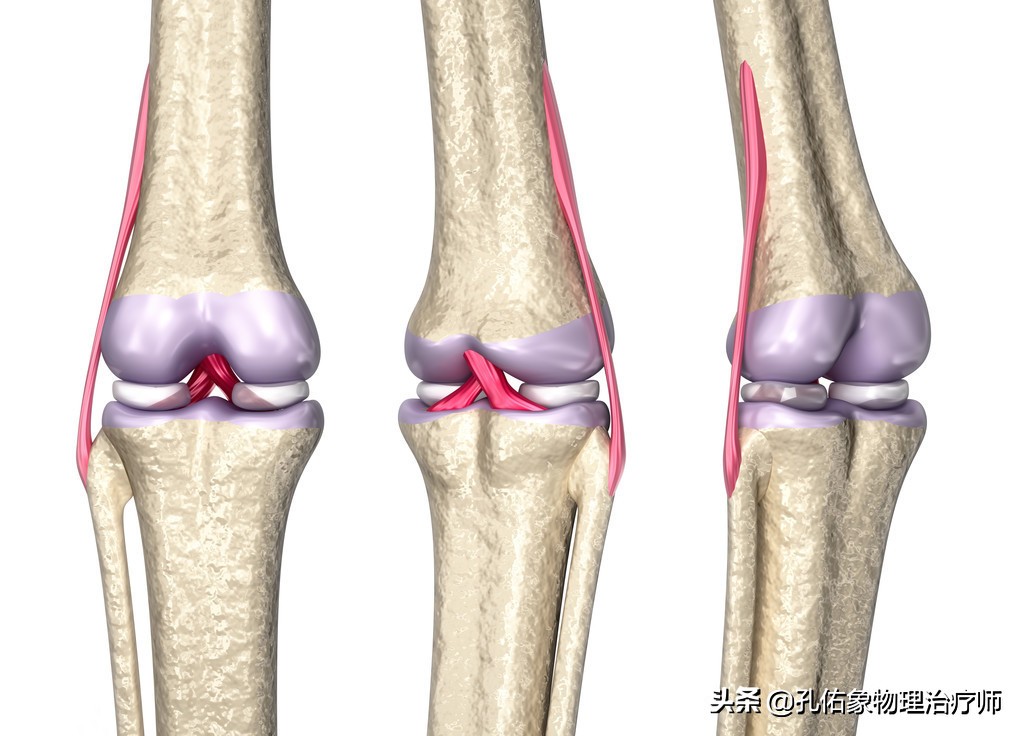

它位于膝关节大腿骨和小腿骨的软骨面之间,半月板在膝关节的内外侧各有一块,它是纤维软骨。其表面是非常光滑的,有一定的弹性。在膝关节屈伸活动的时候,可以帮助膝关节更好的匹配自由运动;同时增加了胫股关节之间的接触面积,减少局部的压力而分担身体的负荷,减少了大腿骨和小腿骨上关节软骨在膝活动时候所承受的摩擦,起着保护膝关节稳定的功能。

如上图所示,是膝关节水平面从上往下看的一个剖面图,前方有前交叉韧带,后方有后交叉韧带,在胫骨平台里面有内侧的半月板和外侧的半月板,前方称为半月板的前角(绿色),后方称为半月板的后角(紫色),不管是内侧半月板还是外侧半月板都有前后角,连接前后角的中间部分是半月板体(红色);所以经常会在膝关节损伤时拍核磁共振显示:半月板的前角损伤,后角损伤或是撕裂,指的就是这些地方,在您脑子里就会有这个映像,因为半月板是我们没办法去用手可触及到的,在外观上,我们也不能用肉眼去看到。